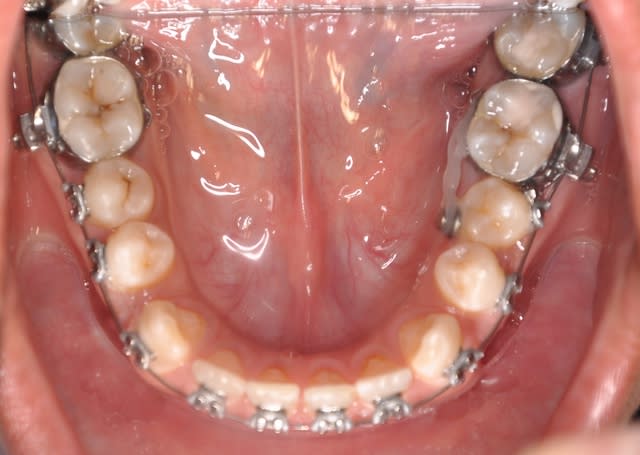

les dernieres photos du cas

- Qu'attends-tu pour fermer les diastèmes en bas ? Il me semble que cela diminuerait la vestibuloversion des incisives supérieures.

il n'y a pas un manque de vertical en postérieur ?

**non, c’est une photo avec miroir qui montre bien les rapport molaires et canines et qui montre le début de la correction de l’articulé en jouant sur le sens transversal de l’arc niti

**oui, je cherche à traiter le coté gauche sans modifier le coté droit

En faite j’ai peur que les élastiques criss-cross me créent une Latérodéviation de la mandibule

Pour moi la mandibule est correcte dans le sens transversal et le problème se situe au niveau du coté maxillaire gauche

Je te dis mon plan de traitement:

*recul des incisives inf. puis sup.

*arc lingual +arc acier de stabilisation inf.

*élastiques criss-cross du coté gauche et box élastique du coté latéral droit